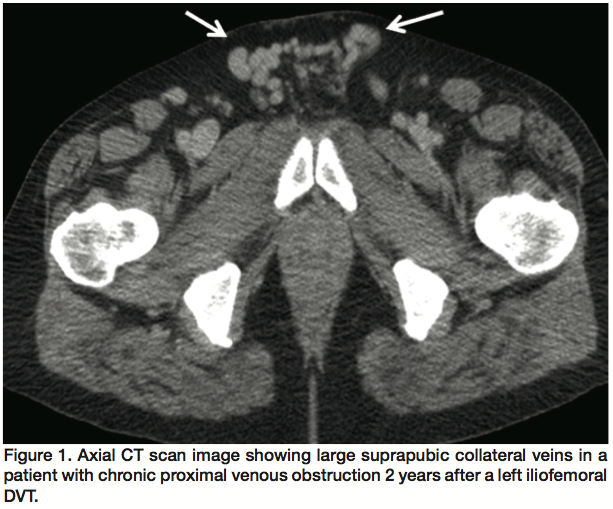

For IVC occlusions or stenosis, we typically employ 18-24 mm Wallstents. Again, the entire diseased segment should be covered. In the event that the occlusion is caused by a thrombosed IVC filter, a wire should be used to cross the thrombosis between the vessel wall and IVC filter, or through the filter itself. Pre-dilatation up to 16-18 atm can be safely attempted to displace or fracture the IVC filter. A Wallstent can then be deployed through the newly created flow channel.14,23 We have also used Palmaz P4010 or P3110 balloon expandable stents (Cordis) to displace occluded IVC filters and reestablish a flow channel, usually in combination with Wallstents (Figure 4).

When IVC obstructions are due to IVC filter thrombosis, displacing or fracturing the filter is recommended for stent placement. In a group of 25 patients with an obstructed IVC filter, the filter was displaced sideways or remodeled and an IVC stent was placed. In this group, 12% had postoperative thrombotic occlusion of their stent. At 54-month follow-up, primary and secondary patency rates in this group were 32% and 42%, repectively.23